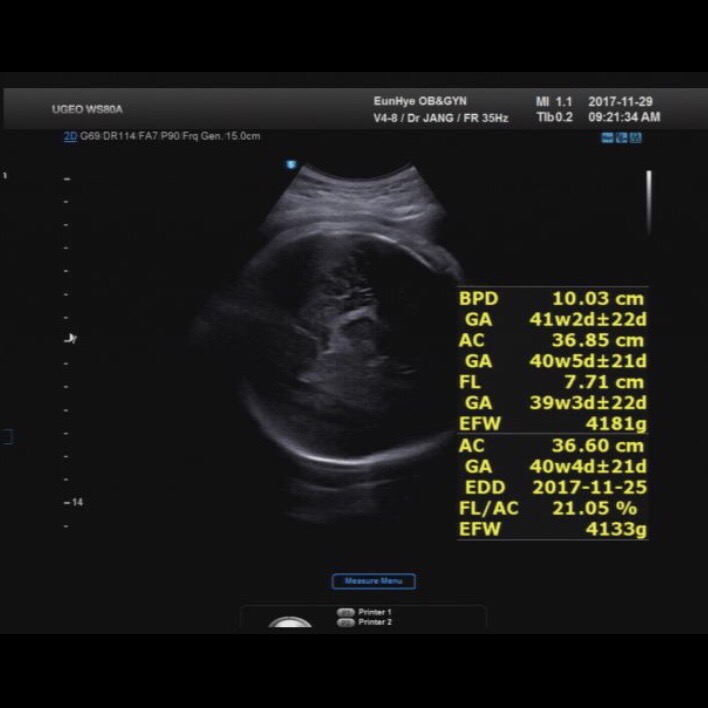

171129 / 37주, 38주 정기검진

171122 / 37주 정기검진37주, 3.6kg를 찍었고 무럭무럭커가는 리로가 고맙기도 했지만, 두려웠다 ㅜㅜㅜ 초...